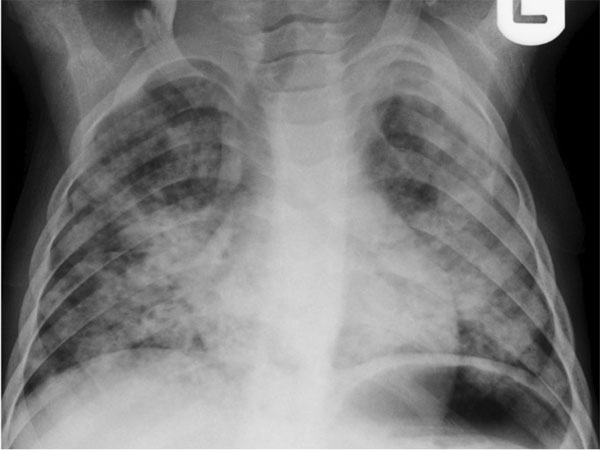

New Delhi, Oct 28: Routine chest X-rays, commonly used to screen for tuberculosis (TB), are failing to detect a large number of asymptomatic cases, according to a new study published in The Lancet Global Health.

Researchers from the University of Cape Town, South Africa, found that standard chest radiographs — even when used alongside symptom-based screening — missed more than 40% of TB cases among people who showed no symptoms but lived with patients diagnosed with pulmonary TB.

The sensitivity of chest radiograph screening for asymptomatic TB was just 56.1%, and combining it with symptom checks increased detection only slightly to 64%, well below the WHO’s target of 90% sensitivity and 70% specificity for effective screening tools.